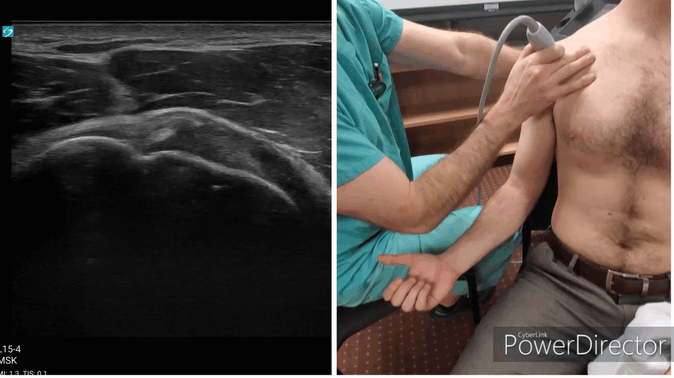

Shoulder Gallery - Biceps Tendon/Bicipital Groove (short axis)

-Positioning: have the patient supinate their arm -Location: Bicipital groove, found via palpation -Hold the ultrasound transverse across the bicipital groove. Slide the probe distally along the groove’s distribution.